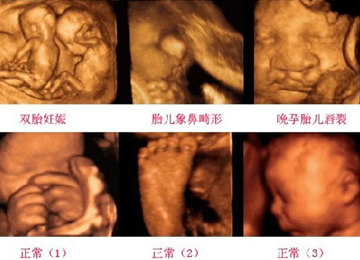

四维彩超是现代妈妈们青睐的一种检查手段,它不仅可以对胎儿进行全面且深入的检查,而且还能为准妈妈们留下胎宝宝生平的第一张照片……下面就来了解一下四维彩超的功用和它的精彩影像吧。

* 四维彩超可以彩色、全方位、透视看到胎儿的颜色、脸部、各器官的发育情况;

* 四维彩超可以动态的观察胎儿在睡眠、活动、打呵欠等等的动作,都可以一次性捕捉;

* 四维彩超可以对胎儿进行早期畸形诊断,如唇裂、腭裂、骨骼发育异常、心血管畸形等胎儿异常进行早期判断。